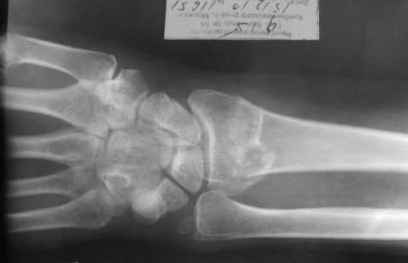

Уважаемые коллеги.Прошу обсудить случай лечения перелома дистального метаэпифиза лучевой кости. Ситуация скандальная и крайне неблагоприятная. Больная с патологической обстоятельностью мышления, склонностью к сутяжничеству, патологическими умозаключениями, не поддающимися коррекции (см. психиатрию, правда офиц. диагноза нет). В данном случае есть ряд ошибок с нашей стороны, прежде всего в отношении качества ведения документации (за что получил административное взыскание, по делом мне дураку). В остальном- придерживались в лечении подхода классический советской школы. Так как умную операцию…… сами знаете… 15.12- перелом луча в Москве. Там же репозиция, гипс. Дальнейшее лечение у нас в ЦРБ. 20.12.- вторичное смещение в гипсе21.12- под внутривенным наркозом- репозиция, гипсовая лонгета. Дальше начинается самое интересное. После репозиции больная заявила, что я (репозицию делал я) порвал ей все связки в суставе, посинел у нее 5 палец, якобы я за него тянул и т. д. На самом деле на 2 сутки после репозиции рука немного отекла и было незначительное сдавление гипсом, который был ослаблен. Дальнейшее лечение консервативное. Через 6 недель- гипс снят, назначено ЛФК. Пациентка крайне недовольна. Говорит, что на снимке у нее выступает кость, я ей сломал руку и.т.д. В общем началось. Пациентка прочитала в интернете наверное все, что есть по данной травме.По заключениями рентгенологов и консультанта из КДЦ областной больницы - стояние отломков допустимое. Объективно говоря- снижена высота лучевой кости, диастаз лучелоктевого сочленения, и не сросся шиловидный отросток. однако на РКТ при сравнении с другой стороной- разница незначительная. Дальше в одной из больниц нашей области и одной из больниц Москвы (вроде бы КГБ 53) врачи сказали, что репозиция сделана плохо. Нужна операция (восстановить длину лучевой кости), даже один из них предложил РЕДРЕССАЦИЮ (хи-хи) с наложением аппарата Илизарова. Что это для данной больной- радость неописанная. (см. описание психического статуса). Ничем другим, кроме зарабатывания дешевого авторитета объяснить данный факт не могу.Кстати, у больной еще нейропатия локтевого нерва.Для разрешения конфликта больная направлена на консультацию в ЦИТО на 03.03.11.

Теперь вопросы: 1.Прошу объективно оценить качество нашей репозиции на момент 21.12. (неужели так плохо?). Что на снимках при снятии гипса- сам вижу. 2. сравнить снимки РКТ (с двух сторон)- так ли велико укорочение лучевой кости и лучелоктевой диастаз. 3. Ваши мнения, в отношении целесообразности оперативного лечения учитывая ВСЕ вышеизложенное. 4. На всякий случай для суда- мог ли я тракцией в 2- 3 кг за 1 и 2 пальцы под внутривенным наркозом неправильно вколотить отломки и травмировать локтевой нерв. Кстати, в США если врач пациенту говорит, что его плохо лечили- то этого врача лишают лицензии. У нас наооборот- обгадить другого милое дело. И это процветает. От себя же могу сказать, что никто в нашем отделении так не поступает. Коллеги, будьте осторожны в своих высказываниях. От осложнений и ошибок никто не застрахован. А в данном случае многое будет зависеть от заключения консультантов поликлиники ЦИТО, куда больная направлена областным травматологом на 03.03 для решения вопроса о дальнейшей тактики лечения. С уважением ко всему травматологическому сообществу Дедок Михаил.